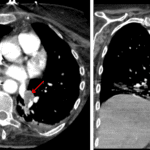

Indication: Acute respiratory failure

CT

Sample ReportFindings consistent with massive aspiration.

Age-indeterminate T9 compression fracture without bony retropulsion. Recommend correlation with point tenderness at this location.